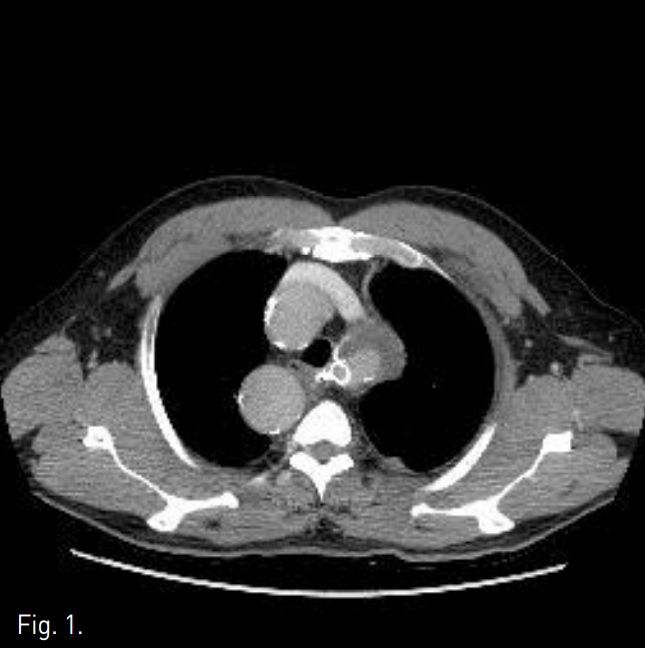

우측 대퇴동맥을 천자하여 8F vascular sheath를 삽입한 후 5F pigtail catheter를 이용한 대동맥조영술에서 하행대동맥에서 기시하는 aberrant left subclavian artery의 분지부 근처에 이전에 삽입한 stent-graft의 중간 부위에서 외측으로 aneurysm sac이 조영됨(Fig. 2A). 0.035-inch 유도철사가 stent-graft를 통과하여 aneurysmal sac내 들어가는 것으로서 stent-graft의 tear 및 type Ⅲ endoleak임을 확인함(Fig. 2B). Stent-graft의 metal component의 fracture는 없었음.

이후 12mm, 6cm 크기의 stent-graft(S&G Biotec, Korea)를 stent-graft내에 endoleak부위를 포함하여 설치한 후 balloon catheter(Foxcross, Abbott, USA)를 이용하여 stent-graft를 확장시킴 (Fig. 2C). 시술 직후 시행한 혈관조영술과 일주일 후에 시행한 CT angiogram에서 더 이상 type II endoleak은 보이지 않았음(Fig. 2D & 3).

Fig. 2

A. Thoracic aortography shows an aneurysmal sac arising at the mid-portion of the aberrant left subclavian artery stent-graft.

B. A 0.035-inch guidewire was advanced into the aneurysm sac, through the stent graft, suggesting type III endoleak.

C. After 12mm, 6cm stent-graft was deployed, the balloon dilatation was done using a balloon catheter.

D. Follow-up subclavian arteriography shows no residual endoleak.